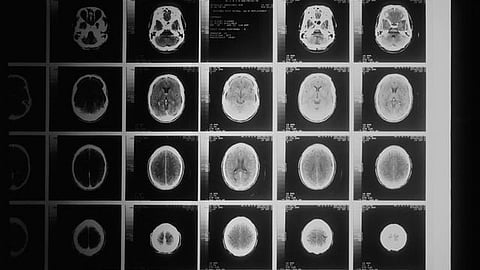

The researchers studied a “spatially-enriched” science course offered at public high schools in Virginia that emphasizes spatial thinking skills, like building maps and planning how cities can be reconfigured to reduce energy consumption. Magnetic Resonance Imaging (MRI) scans showed changes in students’ brains as they learned the course curriculum, and these changes were compared to the ways that learning is traditionally measured (e.g., changes in test scores).

Showing new evidence for MMT in the brain, the research team found that improvements in verbal reasoning could be best predicted by changes in centers of spatial processing in students’ brains – specifically in the posterior parietal cortex.

The research team’s new findings point to a new way of integrating neuroscience with education that helps to overcome these challenges. Instead of focusing on each individual student’s brain, the study focused on the curriculum the students learned. The results show that brain imaging can detect the changes that come with learning a specific curriculum in real-world classrooms, and that these brain changes can be used to compare different curricula.

Students in the spatially-enriched curriculum showed more robust brain changes compared to closely matched students who took other advanced science curricula. These changes appear to indicate a deep learning of spatial abilities that the brain can apply in highly flexible ways, which may not be fully captured by traditional tests of specific skills. In particular, the study’s finding that brain changes can predict learning better than traditional tests provides strong evidence that the inside view afforded by neuroscience can give educators insights about far-transfer learning that they have long sought but that traditional learning assessments often miss.